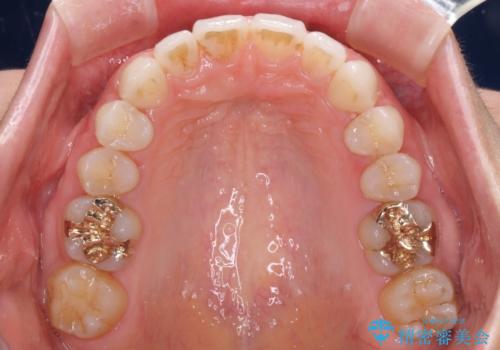

矯正治療後は、奥歯の虫歯や銀歯を補綴・修復治療することとしました。

上顎歯列を下顎に対して4mmほど移動させる必要があったため、治療は長期化することが予想されましたが、患者様にはこちらの期待以上にゴムかけなどに協力いただき、補綴治療も含めて2年強で終えることができました。

PGA(ゴールド)クラウン、インレーの注意事項(リスク・副作用など)

- インレーおよびクラウンは脱離するリスクがあります

- 形成量はセラミックより少ないですが、歯の形成、修復後に歯に症状が出ることがあります

- 自費診療(保険適用外治療)となります